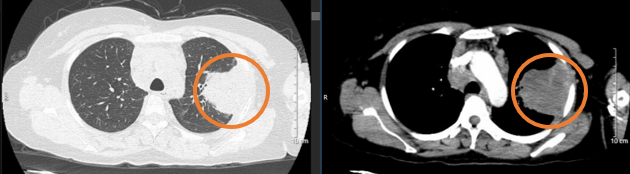

- Chụp cắt lớp vi tính ngực: Hình ảnh u thùy trên phổi trái, kích thước, bờ không đều, sau tiêm ngấm thuốc không đều, cắt cụt các nhánh phế quản. Nhiều hạch trung thất ngấm thuốc viền, kích thước lớn nhất 25x16mm. Hạch thượng đòn hai bên, ngấm thuốc không đều sau tiêm, hạch lớn kích thước 17x14mm.

Hình 1: Hình ảnh chụp cắt lớp vi tính ngực: U thùy trên phổi trái, bờ không đều, sau tiêm ngấm thuốc không đều (vòng tròn màu đỏ).

Chụp cắt lớp vi tính ngực: Hình ảnh u thùy trên phổi trái, kích thước 63x 84mm, sau tiêm ngấm thuốc không đồng nhất, tổn thương xâm lấn vào khí quản cắt cụt một vài nhánh phế quản, xâm lấn màng phổi. Hạch trung thất kích thước 34x39mm

Hình 3: Hình ảnh chụp cắt lớp vi tính ngực sau điều trị hóa chất 3 chu kỳ: U thùy trên phổi trái tăng kích thước so với trước điều trị, xâm lấn màng phổi (vòng tròn màu cam).

Như vậy:  Ở bệnh nhân này, sau điều trị hóa chất phác đồ AI x 03 chu kỳ, xuất hiện tình trạng bệnh tiến triển, thể hiện ở lâm sàng bệnh nhân xuất hiện thêm các triệu chứng (khó thở khi gắng sức, hạch cổ phải tăng kích thước); trên phim chụp cắt lớp vi tính ngực thấy khối u tăng kích thước (từ 48x46mm -> 63x 84mm), xâm lấn vào khí quản, màng phổi, hạch trung thất tăng kích thước (từ 25x16mm -> 34x39mm). Bệnh nhân này đã được hội chẩn hội đồng chuyên môn có chỉ định xạ trị triệu chứng u phổi kết hợp điều trị liệu pháp toàn thân.